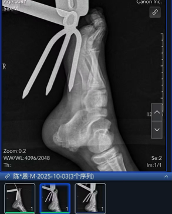

到院后,急诊科医生先对小王的伤口进行了初步清理和检查,随后送往手术室进行异物拔除手术,铁铲虽然扎穿了足底,万幸没有伤到骨头,但术中显示损伤最深达肌肉层。经过一个多小时的手术,扎在足底的铁铲成功取出,术后小王顺利返回病房,目前正在恢复中。

Y91070aixaP8h1h1.jpg